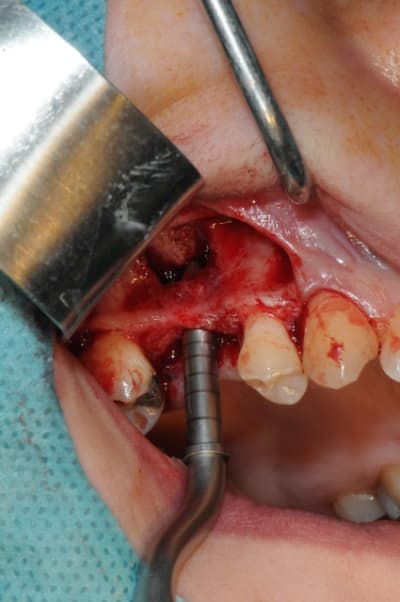

le sujet tombe à pic!

je viens de faire un sinus lift ce matin;

- 3 à 4 mm de hauteur sous sinusienne

- des cloisons de refend partout

- comblement avec du Vital Os

- un implant Axiom D4 L 10

comme je n'avais pas le temps de faire des photos la dernière fois et que j'en étais frustré, je me suis un peu lâcher aujourd'hui...

les premières photos, c'était ouverture par voie latérale